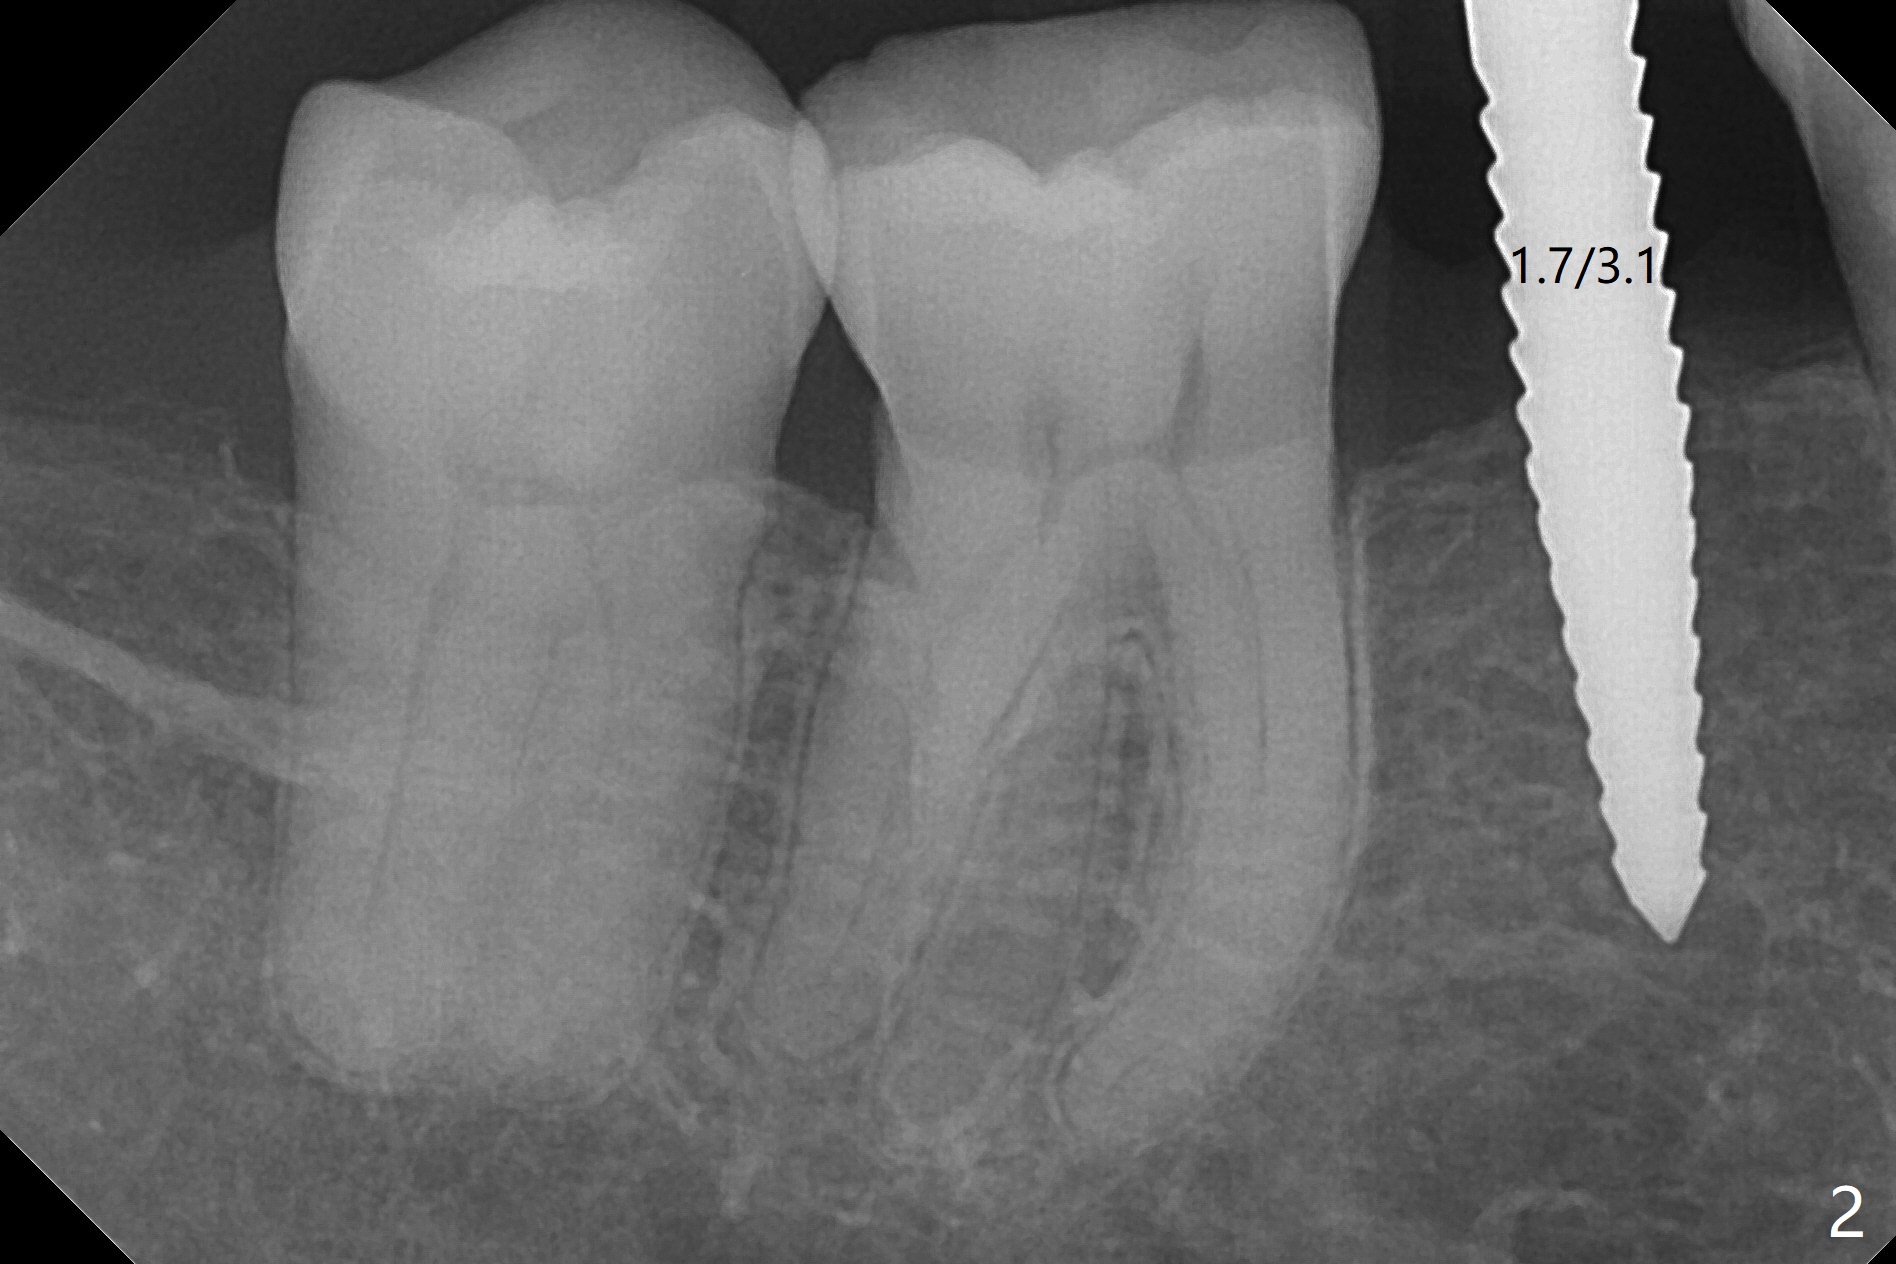

After incision the ridge at #29 is not so narrow as shown in Fig.1. But it is still intact, in contrast to what CBCT shows. Osteotomy is initiated with 1.2 mm drill, followed by 1/1.6, 1.3/2.3 and 1.7/3.1 mm DIO Bone Expanders. In fact mesial and distal crestal slots (BEB: bone expansion and bending) are created by using surgical fissure bur in order to insert the last bone expander in place (10 mm, Fig.2). Following 3.5 mm Cortical Tap, a 3.5x10 mm IS Implant is placed ~ 50 Ncm with clearance from the Mental Loop (Fig.3,4 red dashed line) and slightly subcrestal (Fig.5). The most distal part of the distal slot created for BEB is shown in Fig.5 *. Bone resorption is minimal 4 months postop (Fig.6,7). The implant was apparently placed in the middle buccolingually (Fig.8).